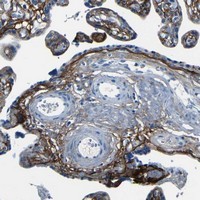

- Immunohistochemical staining of human placenta with FBN2 polyclonal antibody (Cat # PAB20628) shows distinct positivity in basal membranes at 1:10-1:20 dilution.

- Immunohistochemistry (Formalin/PFA-fixed paraffin-embedded sections)